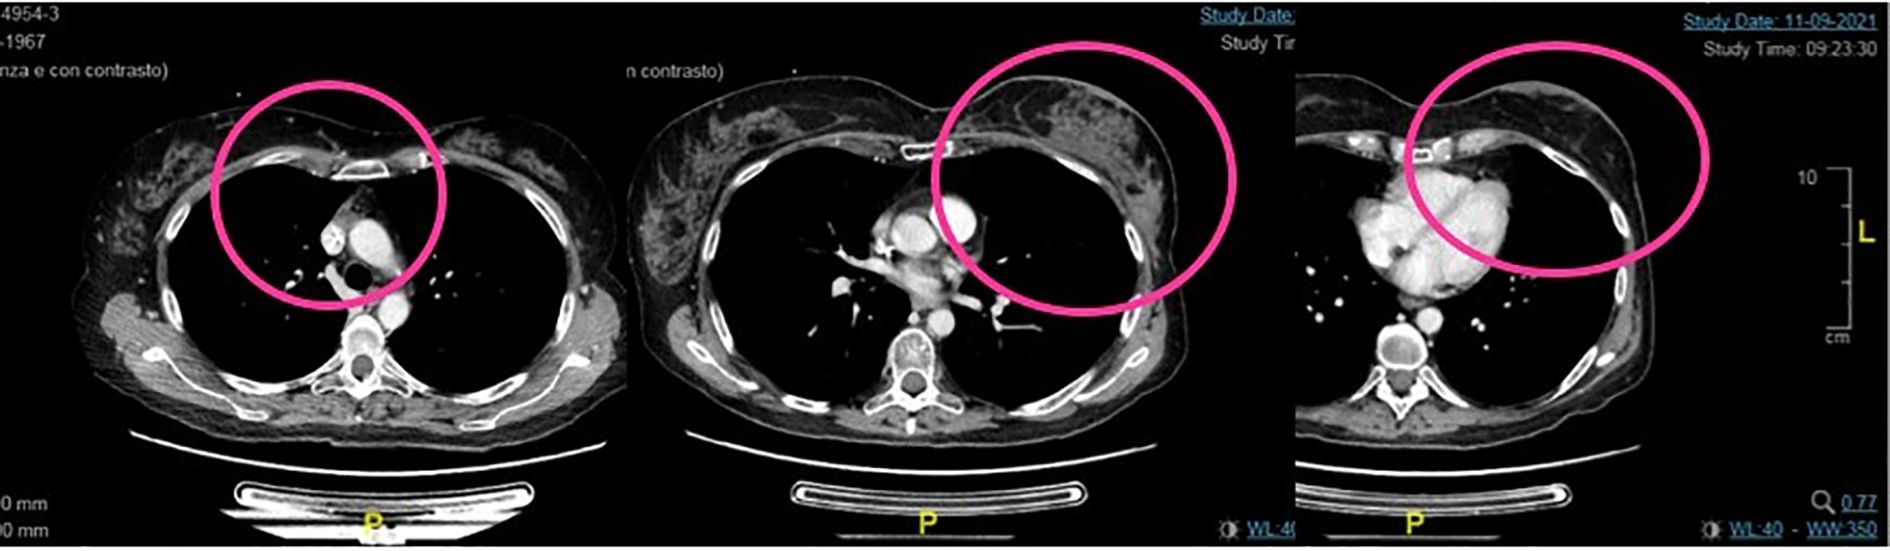

Clinical and radiological benefits lasted until 6 of February 2023 when the patient came to the scheduled visit in ECOG PS 2, reporting new-onset moderate fatigue, moderate cough, and mild dyspnea. Vital signs were in range in the exception of oxygen saturation level that was borderline (94% in ambient area). An emergency chest CT scan showed thickening of the centrilobular and interlobular pulmonary interstitium bilaterally, with associated “tree-in-bud” aspects testifying for bilateral interstitial lung disease grade 3 trastuzumab deruxtecan related (Figure 4).

Figure 4. Second case. Bilateral ILD with greater involvement of basal left lung (upper part of the figure) and ILD initial resolution after high-dose steroid therapy (lower part).

The patient was hospitalized and treated with high flow oxygen therapy, along with infusion of methylprednisolone 1,000 mg/day for 5 days with the addition of broad-spectrum prophylactic antibiotic therapy (levofloxacin 500 mg/day for 10 days).

During hospitalization, there was a progressive improvement in the general clinical conditions with resolution of cough and dyspnea and progressive improvement in thoracic clinic objectivity from the third day of steroid therapy. From 11 of February, the dosage of the infusional steroid was reduced to methylprednisone 1 mg/kg/day (as per ILD trastuzumab deruxtecan guidelines). On February 13, a chest CT showed a marked reduction in phlogosis (Figure 4).